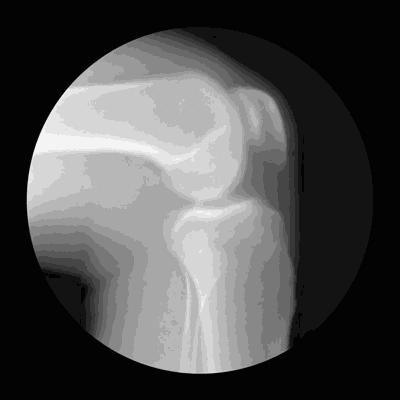

病情如果再进一步发展,关节腔的软骨以及髌骨后方的软骨均有了明显的磨损,会导致髌骨骨骨间隙的狭窄,患者走平路也会出现症状。下图就是比较严重的髌骨股骨关节软骨磨损导致的关节间隙狭窄和软骨丢失。